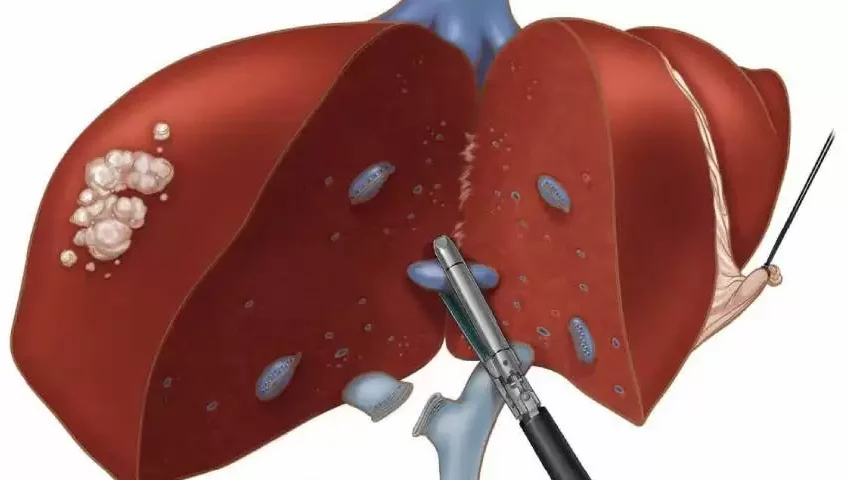

Laparoscopic liver surgery is a minimally invasive “keyhole” approach to removing benign or malignant liver tumors, cysts, or sections of the liver. Using specialized instruments and a camera through small abdominal…

Partial hepatectomy is a surgical procedure to remove a portion of the liver affected by tumors (such as hepatocellular carcinoma or colorectal metastasis), cysts, or damage, while preserving healthy tissue. Due to the…

Liver resection (hepatectomy) is a surgical procedure to remove part of the liver to treat tumors (cancer or benign) or diseased tissue. Because the liver can regenerate, the remaining portion usually…